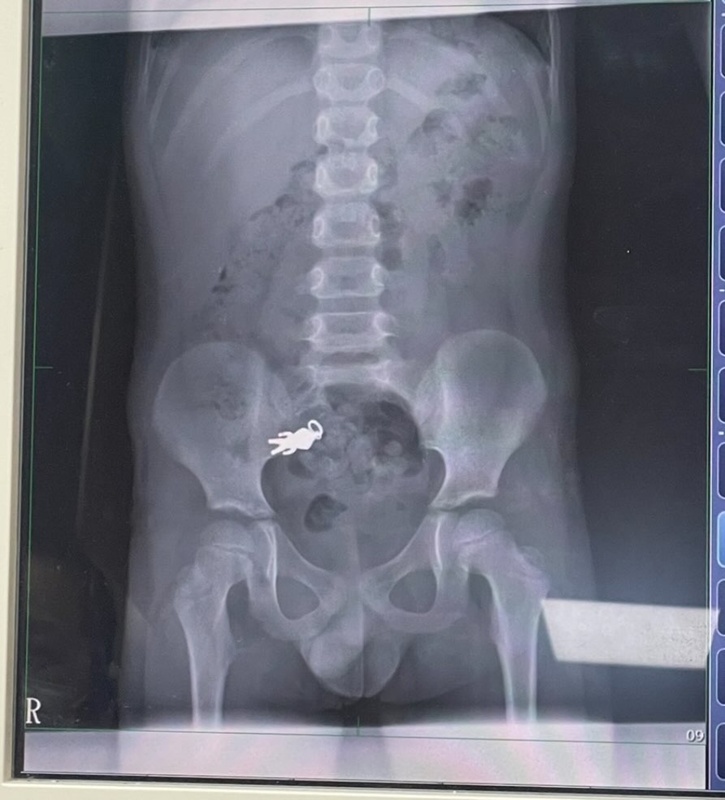

วันที่ 10 กันยายน 2568 เว็บไซต์ CTWANT เผยเรื่องราวสุดแปลกจากครอบครัวหนึ่งในเมืองอี๋หลาน ของไต้หวัน ทางครอบครัวได้พาเด็กชายวัย 7 ขวบไปพบแพทย์ที่โรงพยาบาล ก่อนที่ผลเอกเซเรย์ออกมาจะเป็นภาพที่น่าตกใจไม่น้อย เมื่อมี "ร่างมนุษย์จิ๋ว" อยู่ภายในช่องท้องของเขา ทางครอบครัวต่างรู้สึกเป็นกังวลและเกรงว่าสิ่งแปลกปลอมนี้จะเป็นอันตรายกับลูกชาย

นายแพทย์เซี่ย จินถง แพทย์ผู้รักษา อธิบายว่า วัตถุดังกล่าวมีขนาด สูง 2.8 เซนติเมตร และกว้าง 1.4 เซนติเมตร โดยเคลื่อนตัวผ่านกระเพาะเข้าไปอยู่ในบริเวณลำไส้ของเขาแล้ว ในขณะนั้นสัญญาณชีพของเด็กชายคงที่ และยังไม่มีอาการใด ๆ ทางแพทย์จึงแนะนำให้ครอบครัวพาเด็กชายกลับไปบ้านและติดตามการขับถ่าย หากการขับถ่ายเป็นปกติ ก็ไม่จำเป็นต้องผ่าตัดหรือใช้วิธีฉุกเฉินอื่น ๆ เพื่อช่วยรักษา

ทางครอบครัวได้เผยภาพเอกซเรย์ดังกล่าวผ่านทางบัญชีโซเชียล พร้อมทั้งเล่าเรื่องราวว่า ลูกชายวัย 7 ขวบของพวกเขาเผลอกลืน "เครื่องรางอุลตร้าแมน" เข้าปากไป ขณะที่กำลังนั่งกินคุ้กกี้อยู่หน้าทีวี เมื่อพาลูกชายไปโรงพยาบาล ผลเอกซเรย์จึงปรากฏเป็นภาพที่ดูน่าตกใจ พร้อมทั้งนำภาพของเครื่องรางอุลตร้าแมนเจ้าปัญหามาเปรียบเทียบกับภาพที่อยู่ในท้อง